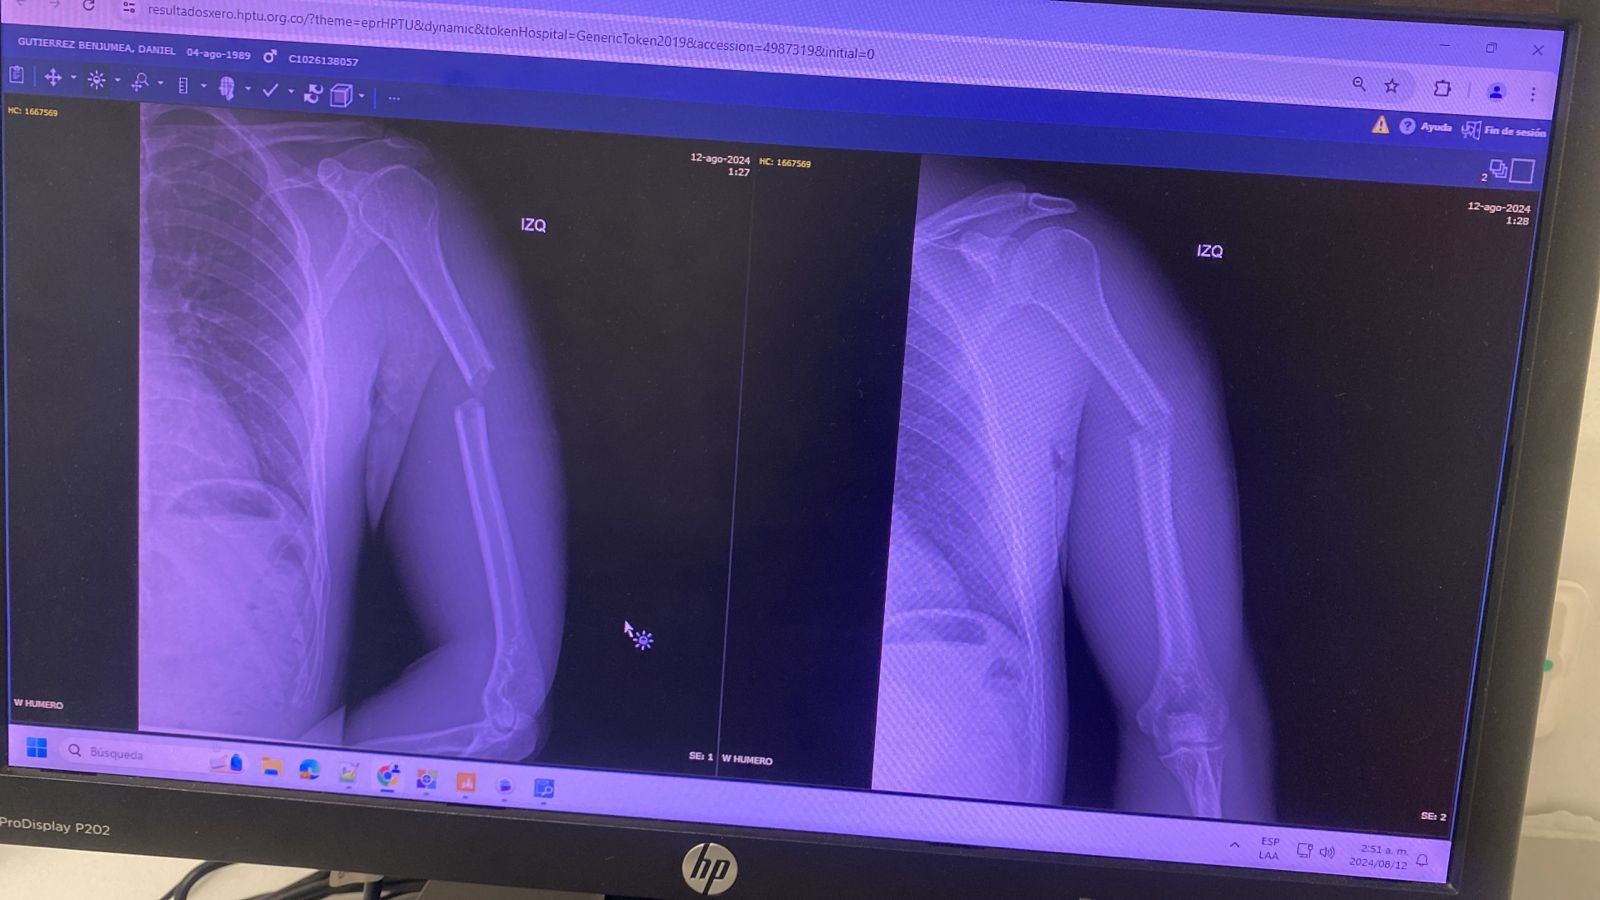

La roca fue lanzada contra el vidrio panorámico frontal del carro y no solamente averió seriamente el cristal, sino que además le ocasionó una delicada fractura en un brazo. "Recibí el impacto en el brazo y quedé en shock, porque mi brazo ni siquiera se movía. Tenía mucha impotencia de no poder moverme normalmente. Hasta pensé que era un mal sueño, sentí mucha rabia e impotencia.", explicó.

Este artista infantil fue atendido y estabilizado inicialmente en el Hospital Pablo Tobón Uribe. Ya fue intervenido quirúrgicamente y la valoración médica señala que requerirá una nueva cirugía por esa lesión en el brazo. Posteriormente requerirá terapia como parte del proceso de rehabilitación.